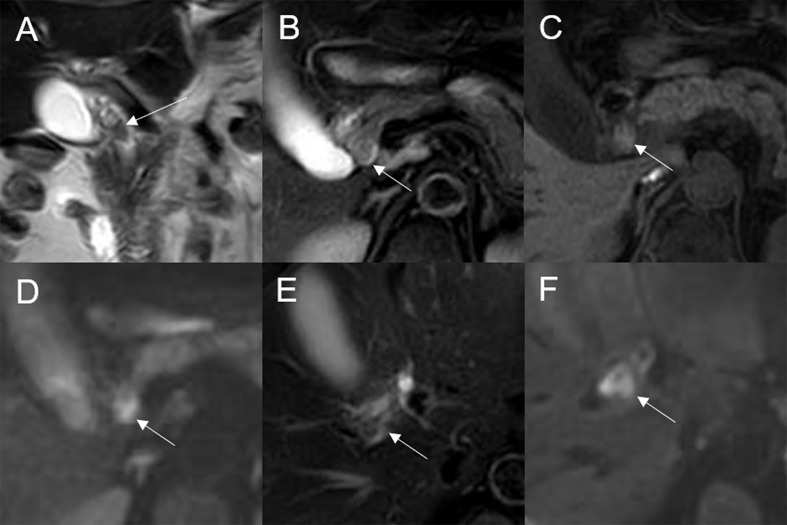

Mean lesion size in the whole sample was 30.83 ± 20.93 mm. All patients presented with an intraluminal ductal mass. While 14/32 (43.75%) lesions presented morphologically as focal eccentric-type masses (f3), 9/32 (28.13%) presented as plaque-like masses, 4/32 (12.50%) as bile duct casting masses, and 5/32 (15.62%) as infiltrative masses. In addition, 8/32 (21.88%) lesions showed a frond-like superficial appearance accompanied by other morphologically categorized appearances other than plaque-like superficial (f4, f5; T2).

On DWI (b = 800 s·mm-2), 5/32 (15.63%) adenomas showed isointensity (f2) and 27/32 (84.37%) showed hyperintensity. In 2/32 (6.25%) cases, the bile duct wall around the lesion showed hyperintensity on DWI (f8). The mean ADC value of the lesions was 1.65 ± 0.38 × 10-3 mm2·s-1 (T2).

Previous studies have found that large gastrointestinal adenomas are easier to manage than smaller ones (ref. 21). However, in this study, we found no significant difference in lesion size between the malignant group and the benign adenoma group. This may have been because the small size of the bile duct lumen results in early clinical symptoms, with detection of the tumor before it becomes large. Plaque-like masses were more common in the benign adenoma group, while infiltrative masses were seen only in the malignant group. Thus, infiltrative behavior may indicate malignant transformation. In two cases in this study, the bile duct wall surrounding the lesion showed hyperintensity on DWI, and pathology confirmed malignant change in the lesion with invasion of the bile duct. This sign was present only in the malignant group. However, there was no significant difference in this sign between the malignant group and the benign adenoma group. Additionally, the other signal characteristics, dilated shape of the bile duct, DWI, enhancement degree, and mode of bile duct adenoma development have limited ability to distinguish malignant transformation of adenoma.